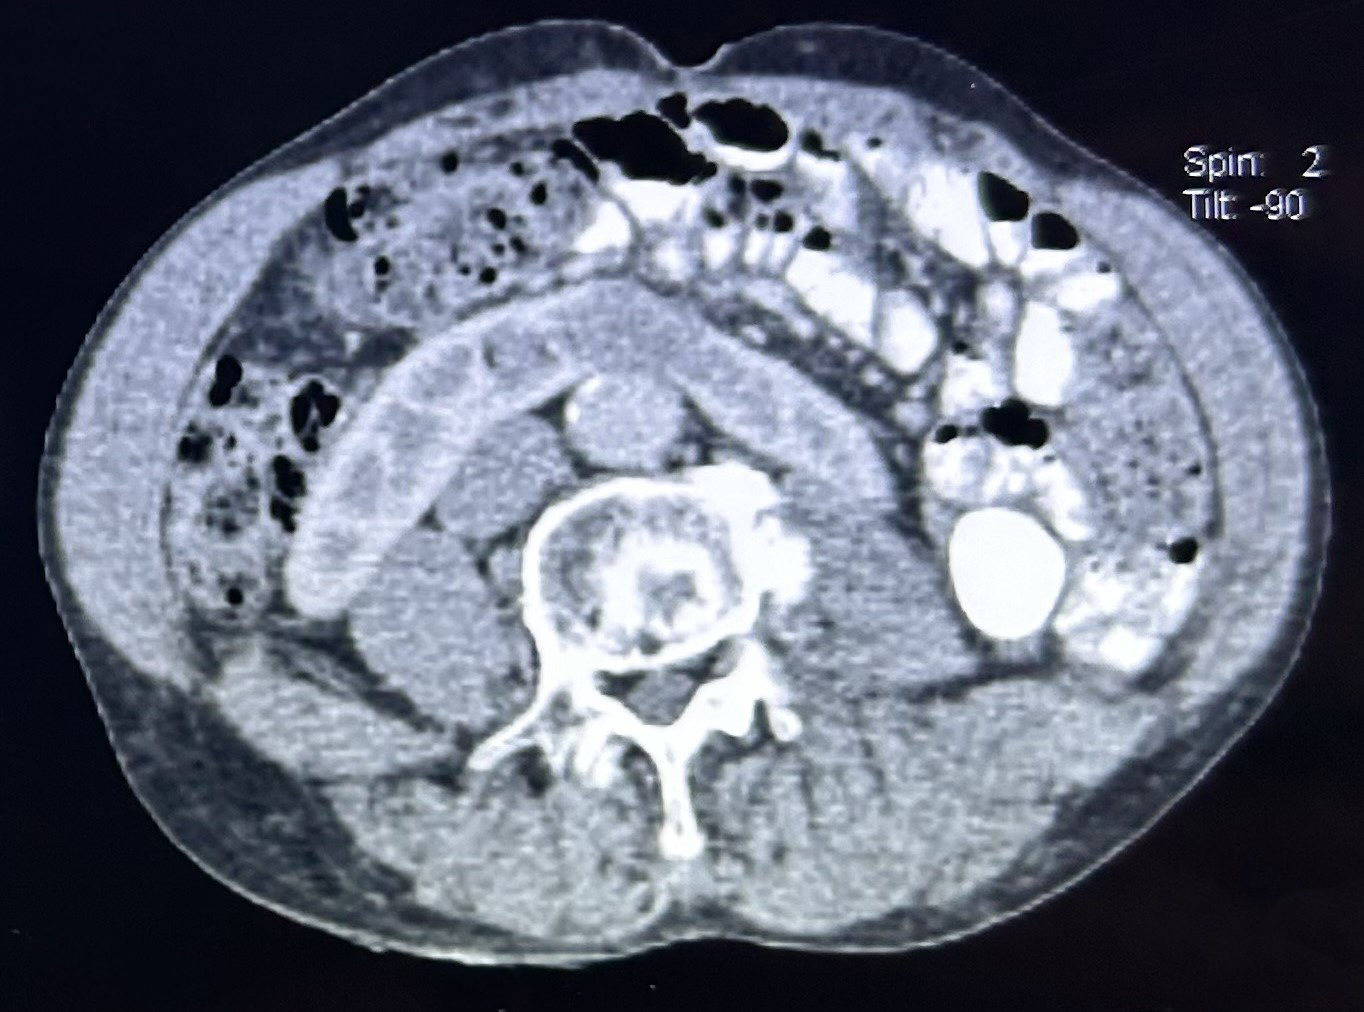

Figure 1. Contrast-enhanced CT scan of the abdomen and pelvis showing a lesion at the isthmus of the horseshoe kidney, consistent with an abscess.

A computed tomography (CT) scan revealed a 2.5 × 3.5 × 3.0 cm abscess at the isthmus of the horseshoe kidney, with associated pyelitis (Figure 1). No prostatic abscess was identified. Urine culture subsequently yielded Burkholderia pseudomallei, confirming melioidosis, while blood cultures remained negative. The patient was treated with intravenous ceftazidime (2 g every 6 hours) for six weeks. A follow-up CT scan demonstrated a reduction in abscess size and resolution of pyelitis. He was discharged on oral co-trimoxazole with scheduled imaging follow-up.